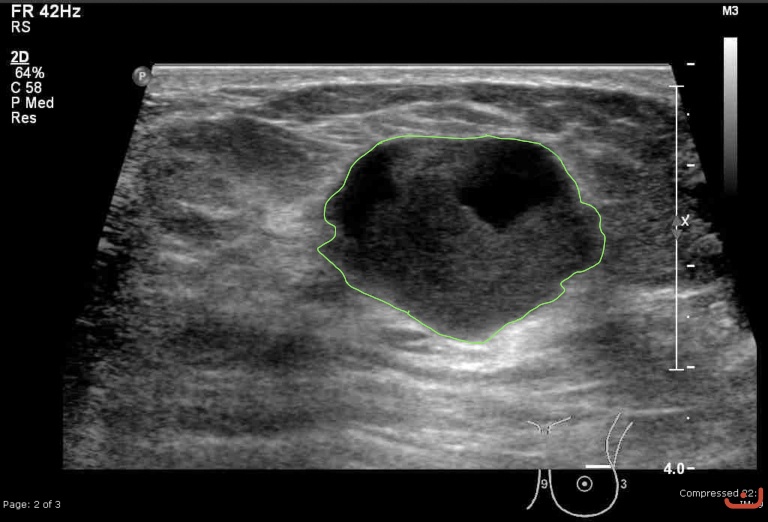

Malignant solid mass